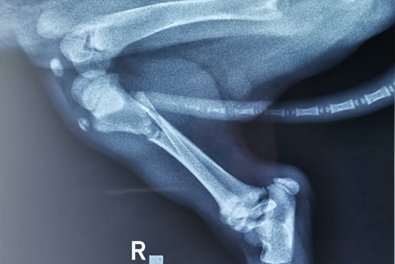

Para la OPMI se optó un implante que abarco la longitud del hueso, se requirió de una placa de bloqueo que se extendió desde la región de la metáfisis proximal hasta la región de la metáfisis distal7. Con la placa radiográfica de la vista lateral medial del miembro posterior derecho, se digitalizo y realizó la planificación pre operatoria de forma virtual. Esta imagen se llevó al programa de vectores CorelDRAW versión X5 para el diseño digital.

En la opción recortar imágenes nos permitió quitar y girar partes para formar la imagen, se alineo el eje central de la tibia tomando en cuenta desde la parte proximal hasta distal seguida del ángulo que forma 90° en la parte proximal se trazó una línea transversal desde la superficie del tubérculo hacia la área intercondilar caudal de la tibia y en su parte distal se trazó una línea transversal desde el borde de la cóclea de la tibia hacia maléolo lateral formando un ángulo de 90° (Figura 2) tomamos de referencia el centro de rotación de la angulación (CORA) para realizar estos trazos del eje central y ángulos.